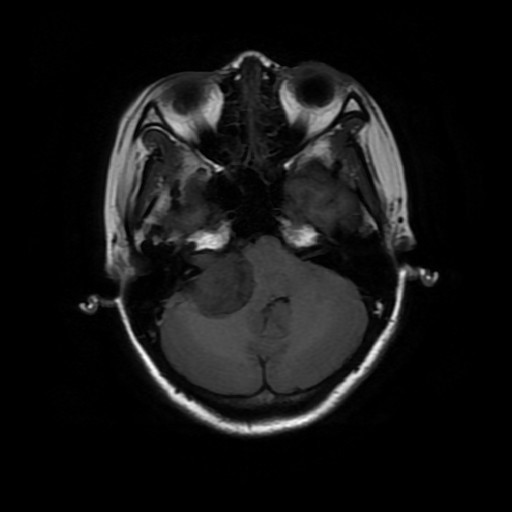

主诉:双眼视物模糊2月余 病史:中年女性,慢性病程。2月前无明显诱因出现双眼视物模糊,当地医院MRI提示:右侧桥小脑角处异常信号,占位,脑膜瘤?胶质瘤?血管母细胞瘤?建议增强扫描。

查体:神志清醒,查体合作。双眼视物模糊,眼球运动无明显异常。双侧瞳孔等大等圆,直径3mm,对光反射灵敏。 辅查:头部CT示:右侧桥小脑角区占位,考虑听神经瘤可能,并梗阻性脑积水。建议进一步MRI检查;头部MR示:右侧桥小脑角区占位,考虑为听神经瘤,并梗阻性脑积水;DTI示脑桥、桥臂及右侧桥小脑角白质纤维束受压移位。

随访:术后病理结果提示:(右侧桥小脑角处肿物)肿瘤由梭形细胞构成,可见疏区及密切,部分细胞呈栅栏状排列,细胞有异型性,核分裂可见,间质有散在淋巴细胞浸润,结合免疫组化结果,符合神经鞘瘤。 讨论:听神经瘤是桥小脑区最常见的肿瘤,也是最常见的脑神经瘤,绝大多数病理类型为神经鞘瘤。下面结合本例影像学习一下其影像表现:首先就是部位,发生于桥小脑区的占位第一反应是听神经瘤,而且和岩骨是呈锐角相交,该征象可以和发生于该部位脑膜瘤鉴别。另外,肿瘤沿听神经长如,导致内听道扩大也是一个重要征象。增强扫描可见明显强化,这可以和发生于该部位的胆脂瘤鉴别。